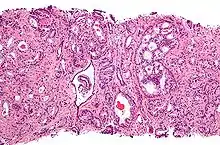

Для развития и целостного функционирования предстательная железа нуждается в андрогенах. Врождённая дисфункция андрогенового рецептора или 5-альфа-редуктазы у мужчин приводит либо к полному отсутствию, либо лишь к минимальному развитию предстательной железы. То же самое верно и для самцов других животных. Через неделю после кастрации предстательная железа самца крысы подвергается дегенерации из-за апоптоза эпителиальных клеток (после удаления семенников уровень андрогенов недостаточен для поддержания целостности простаты). Андрогены также относятся к факторам, стимулирующим развитие рака предстательной железы. Изучение евнухоидных индивидуумов показало, что у них простата остаётся маленькой и не подвергается гипертрофии или злокачественному перерождению. Более того, в животных моделях канцерогенеза в предстательной железе необходимо наличие семенников или экзогенных андрогенов для поддержания развития опухоли. У трансгенных мышей с повышенной экспрессией AR в простате клетки эпителия простаты обновляются гораздо быстрее, чем в норме, и простатическая интраэпителиальная неоплазия (злокачественное новообразование) у таких мышей появляется значительно раньше. Хотя необходимость андрогенов для развития рака простаты не вызывает сомнений, сложно установить связь между относительным уровнем андрогенов в крови и риском развития рака простаты. Для объяснения различий в частоте возникновения и степени выраженности рака простаты были предложены расовые различия в уровне циркулирующих в крови андрогенов. Впрочем, данные по связи между уровнем андрогенов в крови и риском развития рака предстательной железы весьма противоречивы, и окончательного решения по этому вопросу нет. Возможно, противоречивость данных объясняется варьирующей активностью андрогеновых рецепторов, которая может играть исключительно важную роль в развитии рака простаты[11].